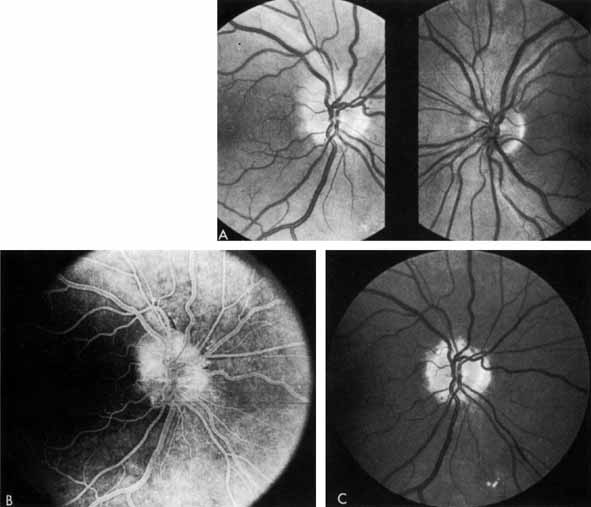

At about the same time, Aiello and co-workers,132,133 and others134–137 noted that patients with unilateral high myopia, extensive chorioretinal scarring, glaucoma, and optic nerve atrophy frequently had markedly asymmetrical retinopathy. The prior retinal or optic nerve damage seemed to protect that eye from diabetic retinopathy (Fig. 21). These investigators initiated the concept of PRP (Fig. 22). They theorized that photocoagulation burns scattered throughout the retina would decrease the retina's need for oxygen and thereby prevent neovascularization from developing or might even cause regression of existent neovascularization. Early studies showing the benefits of PRP were criticized on statistical and other grounds and were not widely accepted.138,139

Fig. 21 A. Right eye of a patient with neovascularization of the disc (NVD), numerous retinal hemorrhages, soft and hard exudates. B. Left eye of the same patient. Note pale optic disc from previous ischemic optic neuropathy and minimal diabetic retinopathy.

Fig. 22 Panretinal photocoagulation.